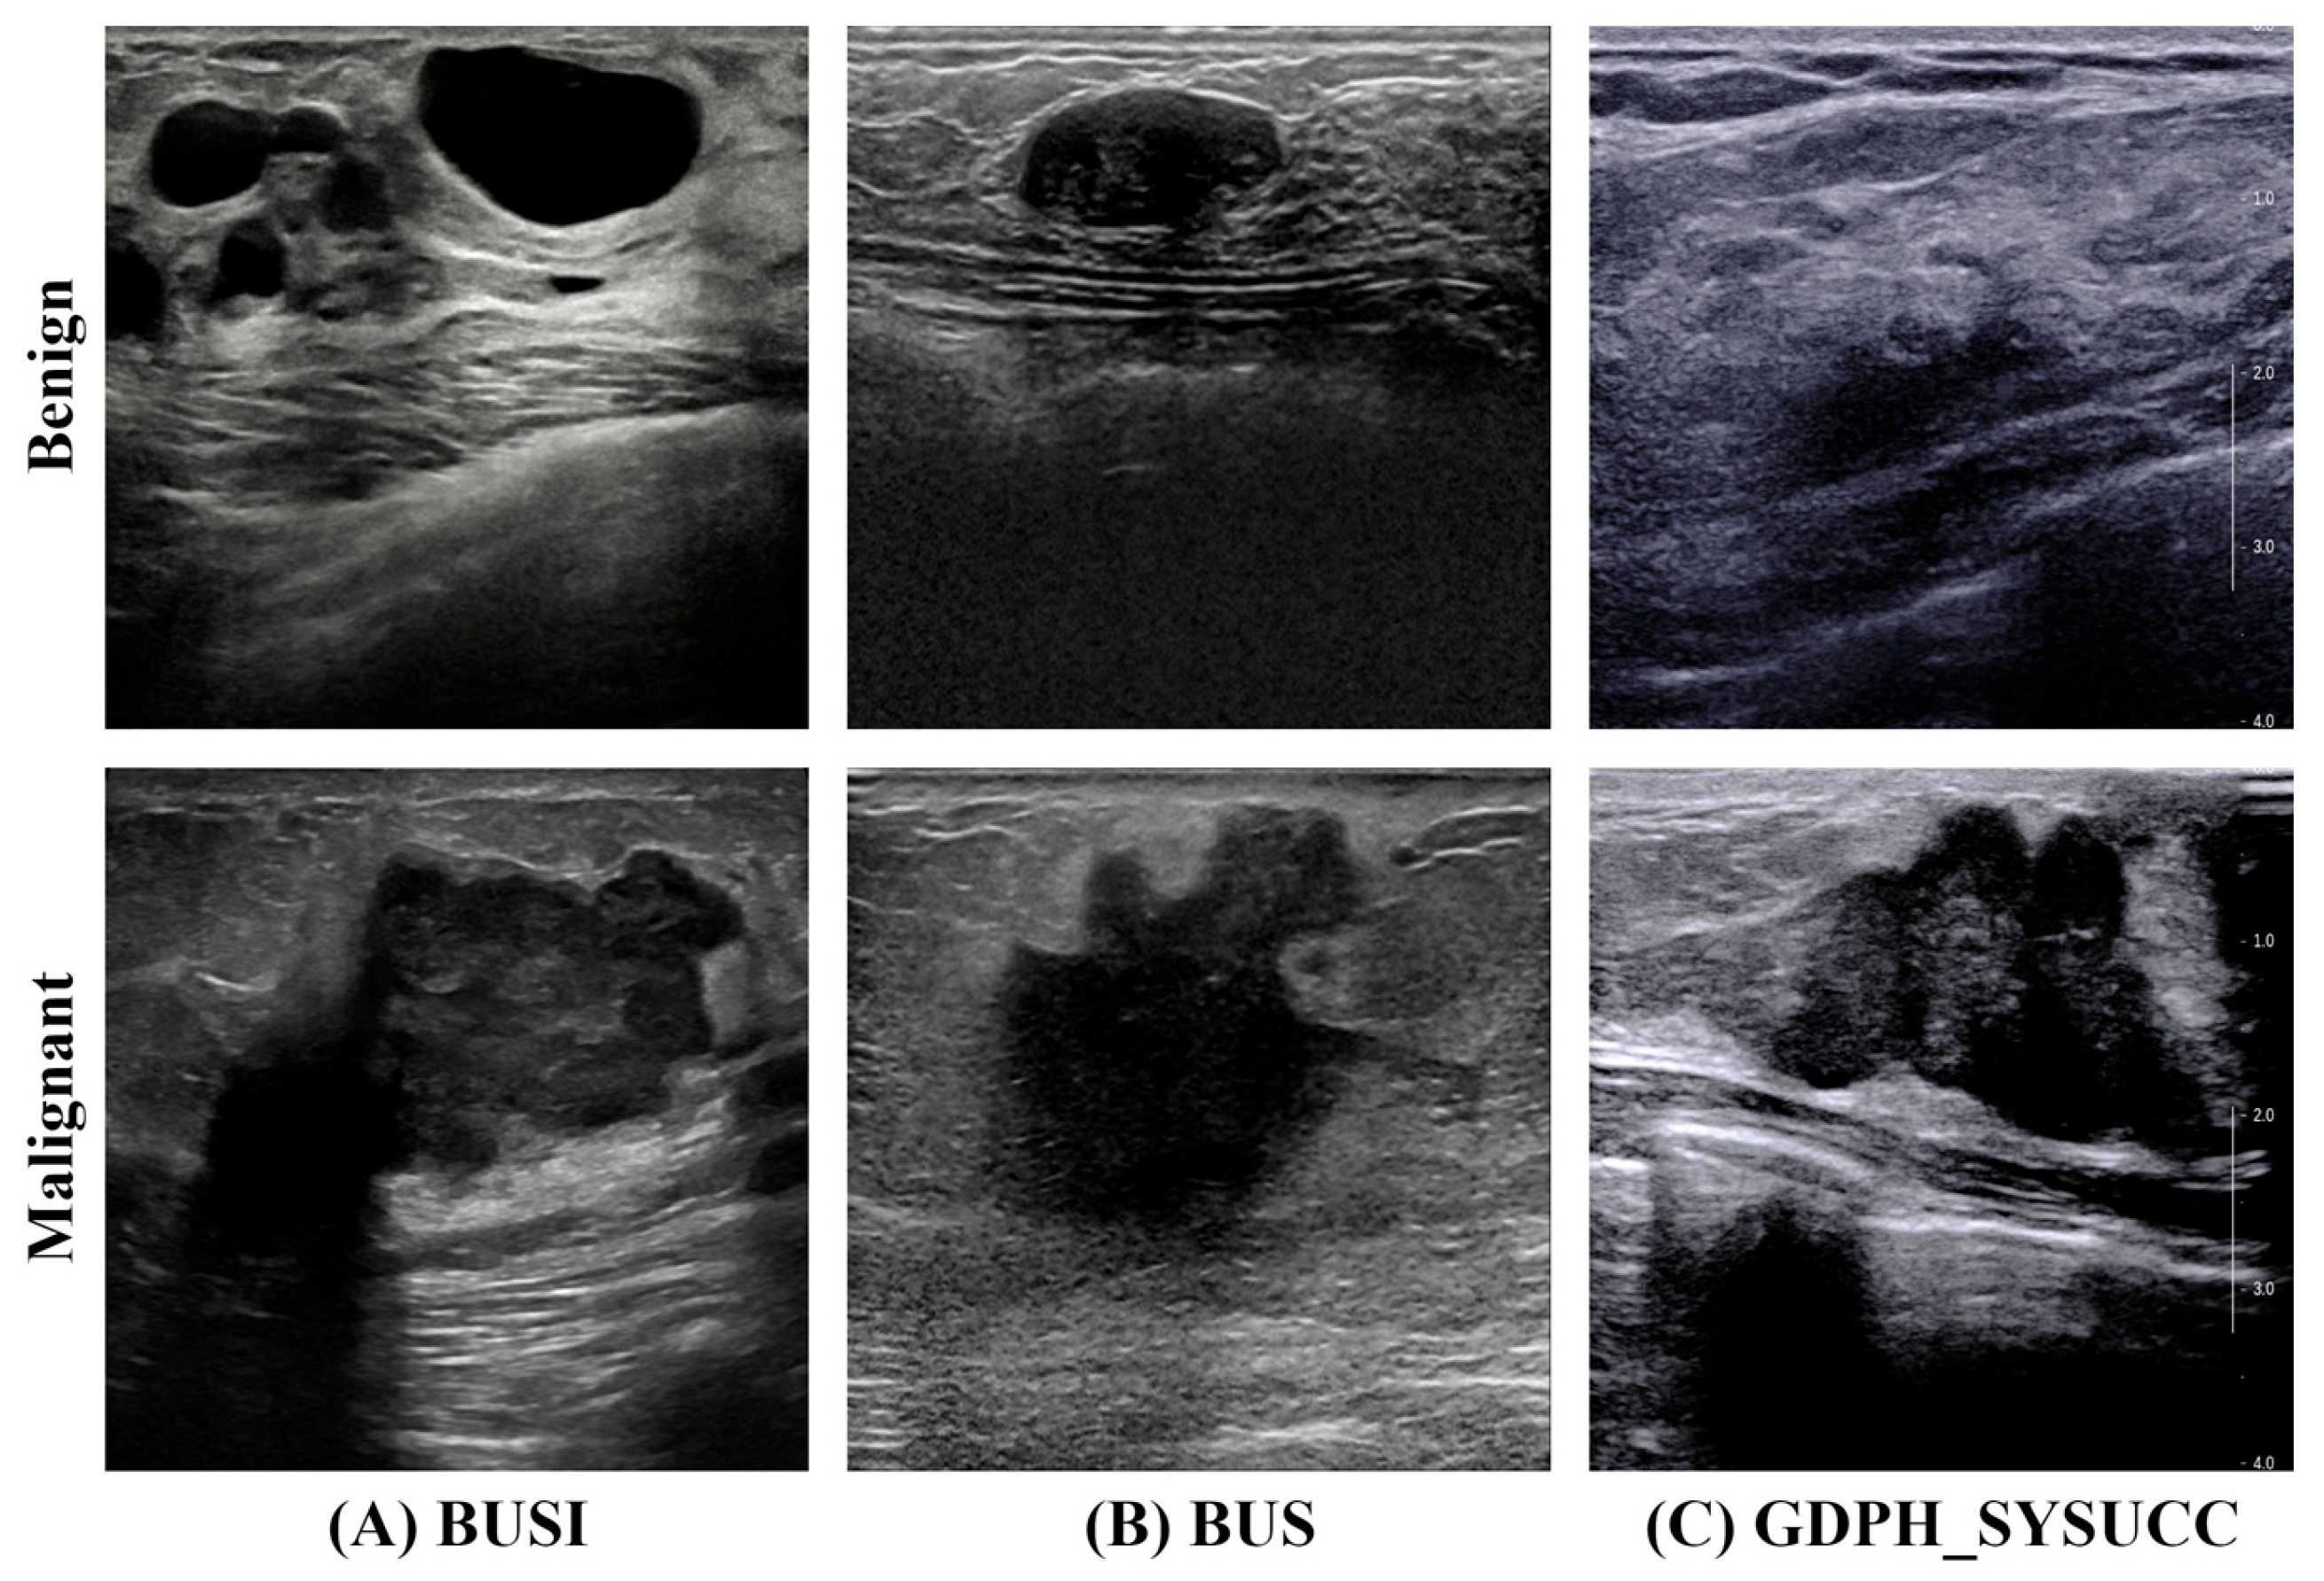

3.1. Dataset

| Category | BUSI | BUS | GDPH_SYSUCC |

|---|---|---|---|

| Number of Images | Number of Images | Number of Images | |

| Benign (Class 0) | 487 | 110 | 886 |

| Malignant (Class 1) | 210 | 53 | 1519 |

| Total | 697 | 163 | 2405 |